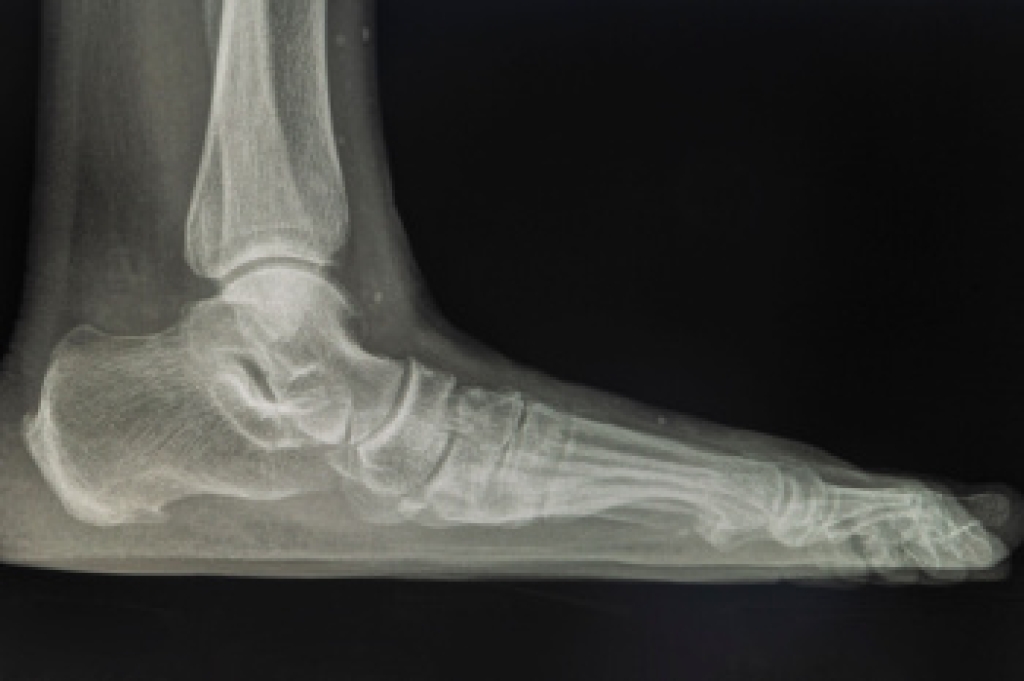

Flatfoot is a condition in which the arch of the foot is depressed and the sole of the foot is almost completely in contact with the ground. About 20-30% of the population generally has flat feet because their arches never formed during growth.

- Flat look to one or both feet